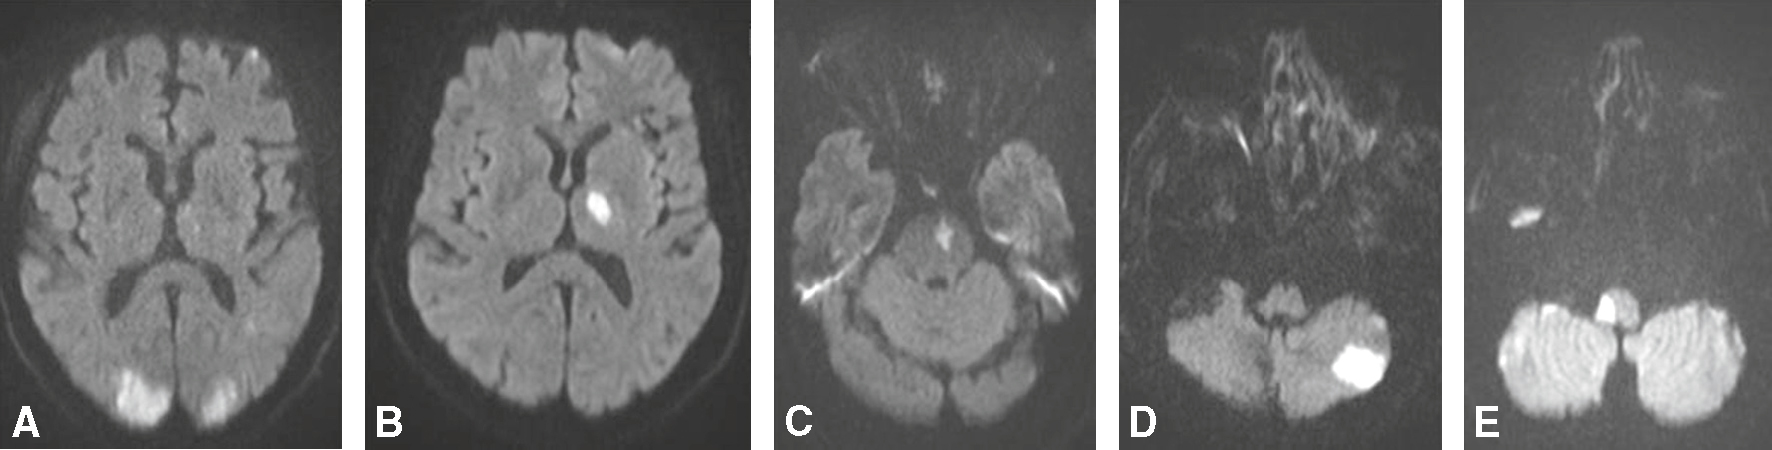

Fig. 28.6 Figure Microangiopathie cérébrale.

A. Infarctus lacunaire récent (IRM séquence de diffusion) hémisphérique droit. B. Infarctus lacunaire ancien (IRM séquence FLAIR). C. Leucoencéphalopathie vasculaire (IRM séquence FLAIR). D. Microbleeds (microsaignement) (IRM séquence T2*).

Fig. 28.7 Figure Hémorragies intracérébrales.

A. Hématome sous-cortical de l’HTA en scanner. B. Hématome sous-cortical de l’HTA en IRM (séquence T2*). C. Hématome lobaire de l’angiopathie amyloïde en scanner. D. Hématome lobaire de l’angiopathie amyloïde en IRM (séquence T2*).

Fig. 28.10 Figure Thrombose veineuse cérébrale.

A. Thrombose du sinus latéral gauche en scanner sans injection. B. Infarctus veineux hémorragique en scanner. C. Infarctus veineux en séquence IRM FLAIR. D. Infarctus veineux avec remaniement hémorragique en séquence IRM T2*. E. Infarctus veineux avec remaniement hémorragique en séquence IRM diffusion. F. Thrombose du sinus latéral gauche en séquence IRM T1 après injection de gadolinium.

Fig. 28.11 Figure Signes précoces d’ischémie cérébrale en IRM.

A. Hyperintensité en séquence de diffusion. B. Hypo-intensité (œdème cytotoxique) en séquence ADC (coefficient apparent de diffusion). C. Imagerie subnormale en séquence FLAIR. D. Absence d’anomalie en séquence T2*.